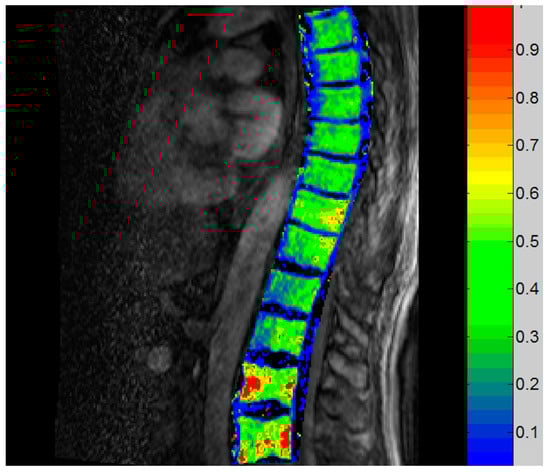

3.3. Imaging Results

3.3.3. Vertebral DCE-MRI

| DCE-MRI | Th 7/9, L1 | Ktrans, Ve, Kep |

| 15O-water PET | Th 5/7/9 | Blood flow in ml/min/ml |